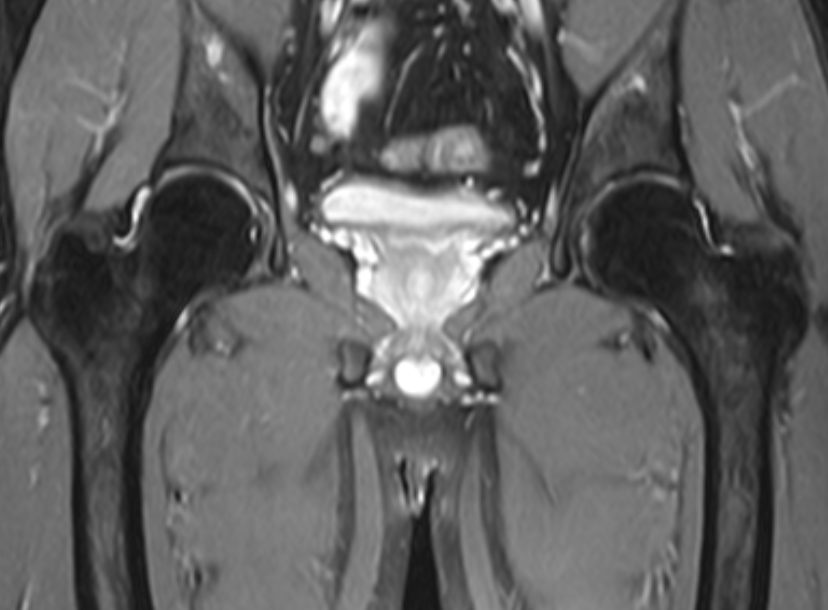

髋关节-fs T2